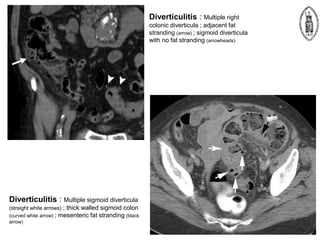

Diverticulitis

 One of the most common causes of acute

abdominal pain in the elderly

 Left and sigmoid colon predominantly affected

 Less commonly right colon and cecum may be

affected – mimicking appendicitis

 CT investigation of choice

– Asymmetric or circumferential colonic wall thickening

– Associated focal pericolic fat stranding

– Inflammed diverticulum often visible at level of

maximal fat stranding

– Normal appendix is important in differentiating from

appendicitis

– Pericolic lymphnodes suggests malignancy rather than

Diverticulitis : Multiple right

colonic diverticula ; adjacent fat

stranding (arrow) ; sigmoid diverticula

with no fat stranding (arrowheads)

Diverticulitis : Multiple sigmoid diverticula

(straight white arrows) ; thick walled sigmoid colon

(curved white arrow) ; mesenteric fat stranding (black

arrow)

Diverticulitis : Multipleright colonic diverticula ; adjacent fat stranding (arrow) ; sigmoid diverticula with no fat stranding (arrowheads) Diverticulitis : Multiple sigmoid diverticula (straight white arrows) ; thick walled sigmoid colon (curved white arrow) ; mesenteric fat stranding (black arrow)